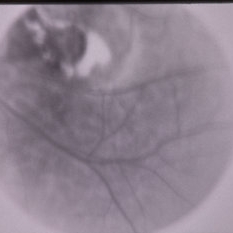

FA of Linear Sebaceous Nevus of Jadassohn

FA of Linear Sebaceous Nevus of Jadassohn

Feb 20 2015 by H. Michael Lambert, MD

FA of linear sebaceous nevus.

Condition/keywords: choroidal defect, linear nevus sebaceous syndrome